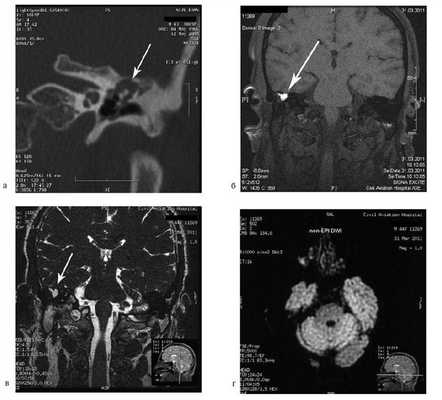

Рис. 1. КТ височных костей пациентки М. а — коронарная проекция: деструктивная полость в пирамиде височной кости, заполненная субстратом неоднородной плотности, капсула лабиринта значительно разрушена на уровне базального и апикального завитков улитки, латерального и верхнего полукружных каналов; б — аксиальная проекция: деструктивная полость с разрушением задней грани пирамиды, передневерхней и нижней поверхности.

По результатам МРТ головного мозга правая пирамида височной кости деформирована, увеличена в объеме, выполнена субстратом размером до 5,5—2,8—3 см, распространяющимся на область внутреннего слухового прохода, заднего полукружного канала, медиальные отделы барабанной полости, сосцевидный отросток. Описанный субстрат изо-гипоинтенсивен в режиме Т1, гиперинтенсивен — в Т2 и non-EPI DWI (рис. 2). Заключение: признаки рецидива холестеатомы с деструктивными изменениями структур внутреннего и среднего уха на фоне хронических воспалительных изменений.

Рис. 2. Магнитно-резонансная томография головного мозга пациентки М. Деформированная, увеличенная в объеме пирамида височной кости выполнена мягкотканым субстратом.